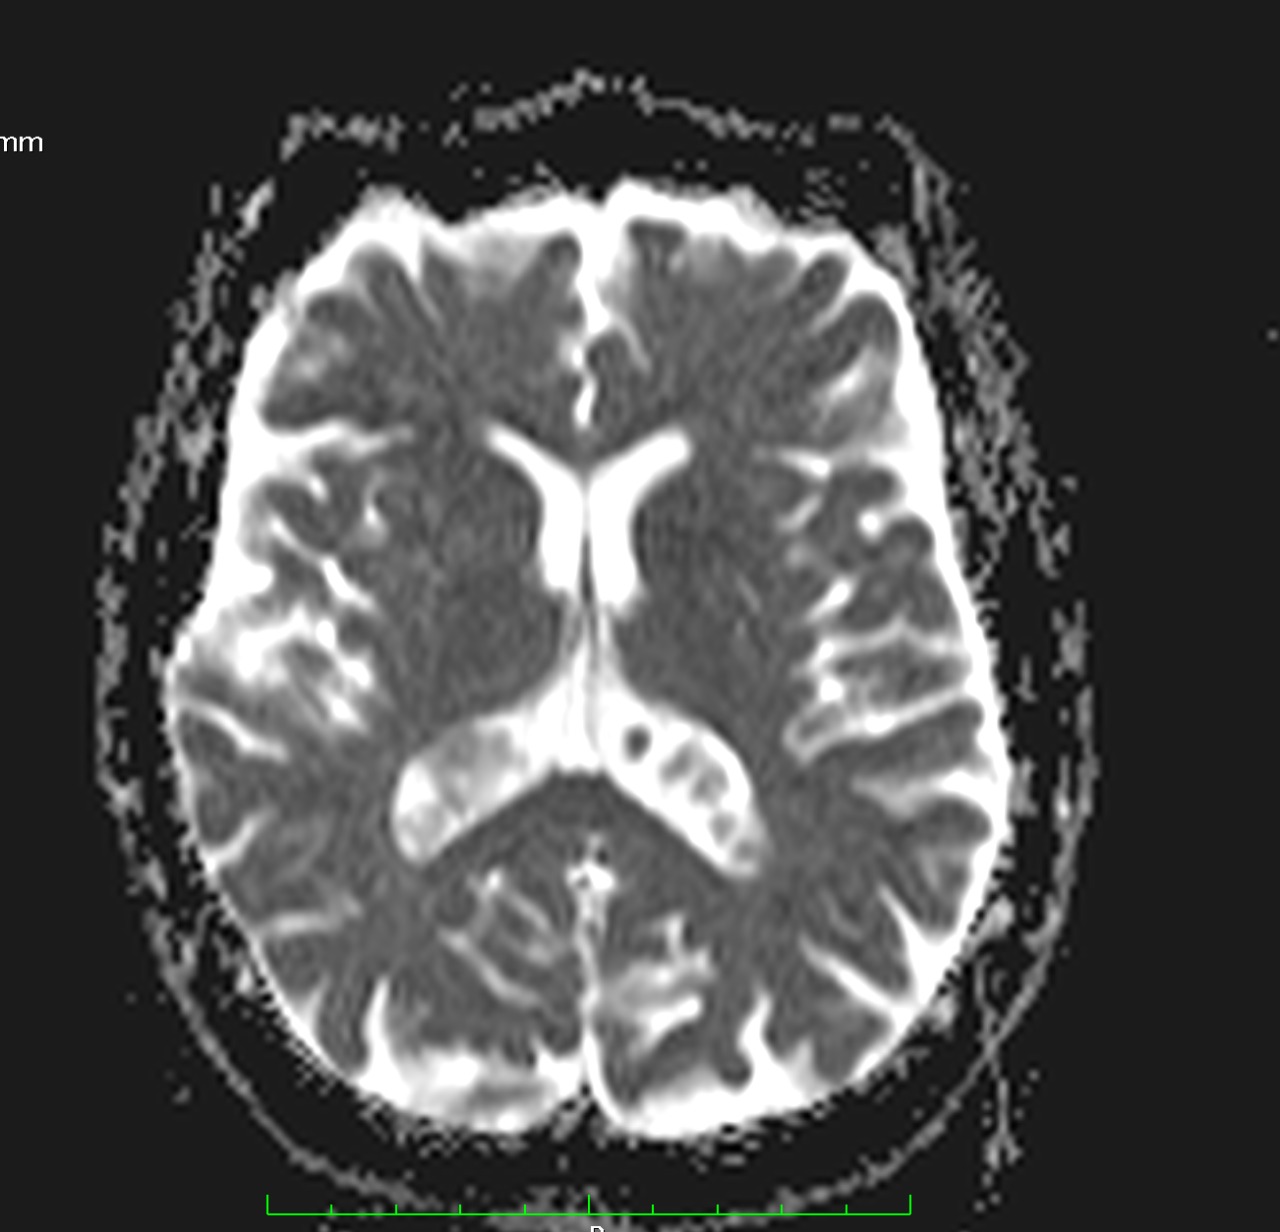

Son pseudolesiones frecuentemente observadas en estudios de neuroimagen.

Sus principales características son:

✔ Lesiones intraventriculares

✔Bilaterales

✔65% restringen en la secuencia de difusión

✔ Realce variable posterior a la administración de medio de contraste

✔ No hay edema del parenquima adyacente

NO DEBEN CONFUNDIRSE CON LESIONES TUMORALES INTRAVENTRICULARES!!!!